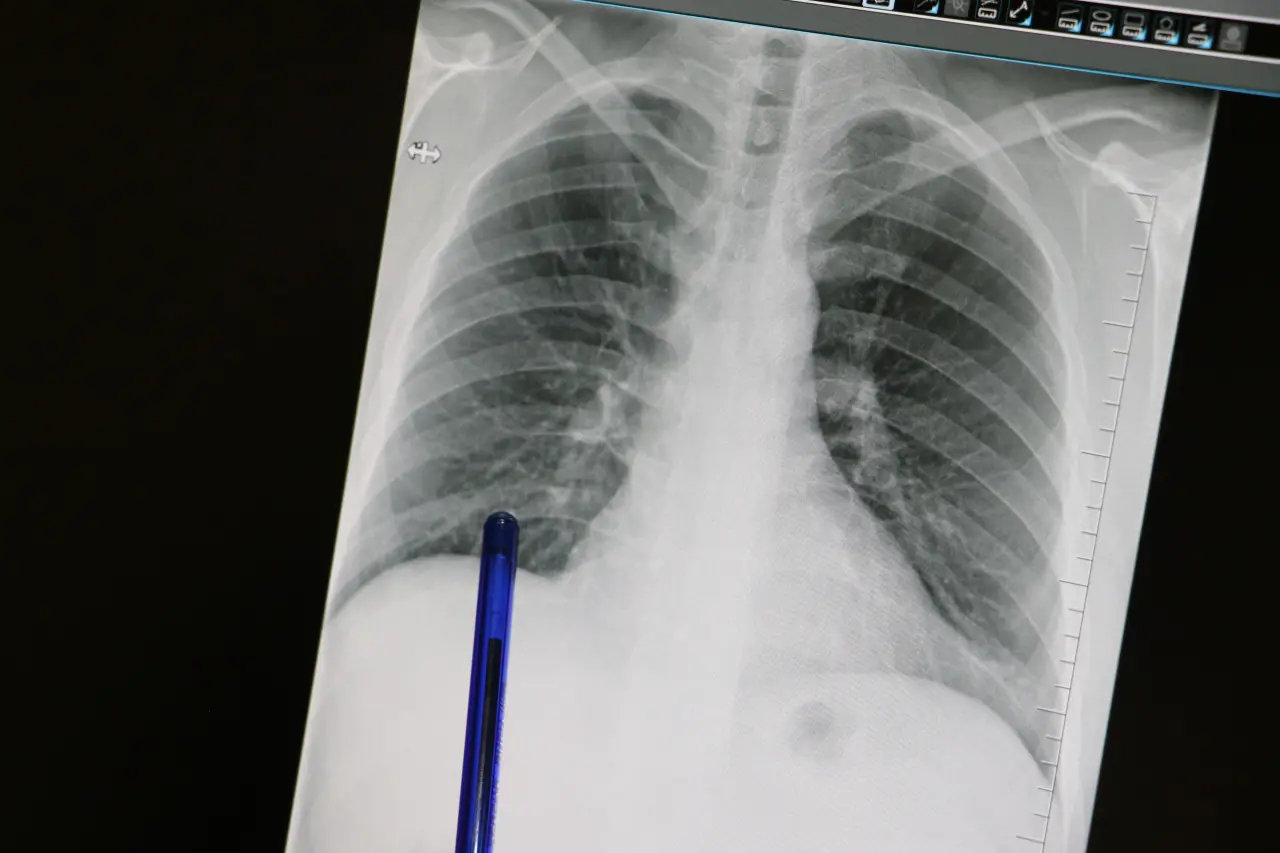

Akciğer kanseri ise akciğer dokusundaki hücrelerin kontrolsüz çoğalmasıyla oluşan ve diğer organlara yayılabilen ciddi bir hastalık olarak biliniyor. Genellikle erken evrelerde belirti vermediği için geç fark ediliyor ve bu durumda tedavi şansını azaltıyor. En önemli risk faktörü sigara kullanımı olsa da, sigara içmeyen kişilerde de bu hastalık görülebiliyor.

"Bu hastalık, hem dünyada hem de ülkemizde kansere bağlı ölümlerin en sık nedenidir. Ne yazık ki genellikle erken evrede belirti vermediği için geç tanı alabilmekte ve bu da tedavi şansının azalmasına sebep olabilmektedir"

"Bu hastalık, hem dünyada hem de ülkemizde kansere bağlı ölümlerin en sık nedenidir. Ne yazık ki genellikle erken evrede belirti vermediği için geç tanı alabilmekte ve bu da tedavi şansının azalmasına sebep olabilmektedir. Akciğer kanserlerinin büyük kısmı, neredeyse yüzde 85-90 kadarı bilindiği üzere sigarayla ilişkilidir. Günde içilen sigara sayısı ve kullanım süresi arttıkça risk de katlanarak artar. Ancak hiç sigara içmeyenlerde de pasif içicilik de en az aktif içicilik kadar önemli bir faktördür. Elektronik sigaralar ya da ısıtılmış tütün ürünleri de sanıldığı gibi güvenli değildir. Nikotin içerdikleri için bağımlılığı sürdürürler ve ekstra pek çok kimyasal daha içerirler. Uzun vadeli zararları henüz tam olarak bilinmemektedir"

"Akciğer kanserinin en sık belirtileri ise uzun süren öksürük, balgamda kan, nefes darlığı, kilo kaybı ve göğüs ağrısıdır. Özellikle sigara içen birinde yeni başlayan ya da karakteri değişen öksürük varsa mutlaka bir göğüs hastalıkları uzmanı tarafından değerlendirilmelidir. Erken tanı her kanser türünde olduğu gibi akciğer kanserinde de hayat kurtarır. 50 yaş üzeri ve uzun süre özellikle 20 paket yıl ve daha fazla sigara içmiş kişilerde düşük doz tomografi ile tarama yapılması, hastalığın erken evrede erken tanı sağlar ve tedavi şansını ciddi şekilde artırır. Sigarayı bırakmak her yaşta faydalıdır. Bıraktıktan sonraki on yıl içinde akciğer kanseri riski büyük oranda azalır. Çalışmalar 10 yıl sonra yüzde 50, 15 yıl sonra ise yüzde 90'a kadar akciğer kanseri riskinin azaldığını göstermiştir. Sigara içen bireylerde sabahları balgam ve öksürükler mevcut oluyor. Bu durumlarda balgamın karakter değiştirmesi ve artması önemli bir belirti olabiliyor"